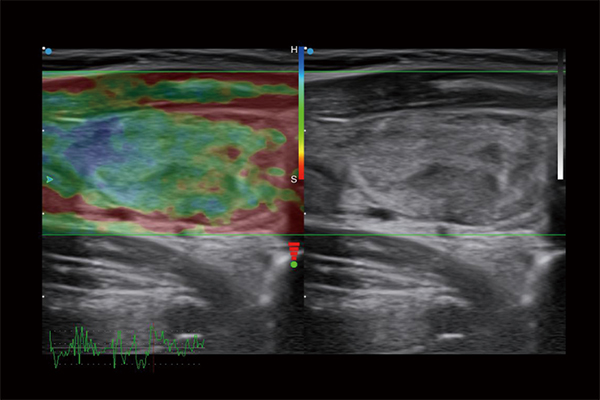

Full Volume Imaging and Coronal Section with High Clinical Value

IBUS acquires volume data from multiple sections to provide abundant information. The coronal section intuitively shows the anatomical information of breast tissue in a supine position during operation, which helps surgeon to perform more accurate surgical planning.

Intelligent Breast Solutions on the Workstation

Automatic lesion detection powered by AI identifies suspected area and traces the lesion from multiple sections. Quantitative coordinate position and graphic indication will be displayed for precise lesion localization.

Lesion stereo images are generated from volume data rendering. It provides intuitive and detailed information for better observation and lesion localization.

Lesion correlation correlates the information obtained from different scanning positions and sections to avoid misdiagnosis.